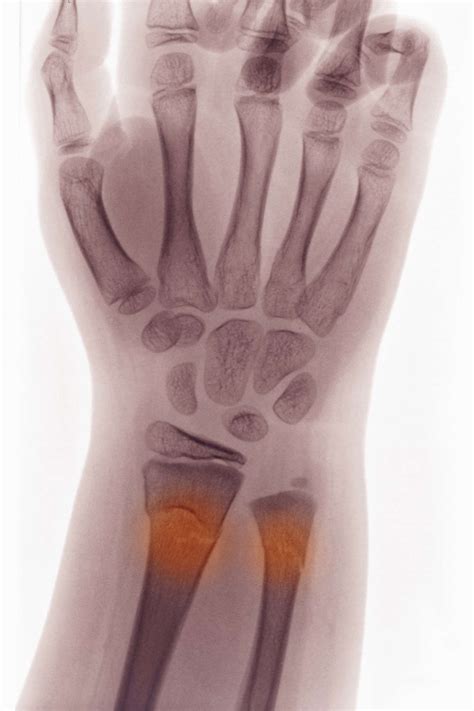

A buckle break wrist, or torus fracture, is a type of fracture that occurs when the bone buckles or compresses under pressure. This type of injury is common in children and adolescents because their bones are still growing and are more flexible. The most common site for a buckle break wrist is the distal radius, which is the larger of the two bones in the forearm that connects to the wrist.

If you suspect a buckle break wrist, it is important to seek medical attention immediately. A healthcare professional will perform a physical examination and may order an X-ray to confirm the diagnosis.

• Order an X-ray to visualize the fracture and determine its severity.